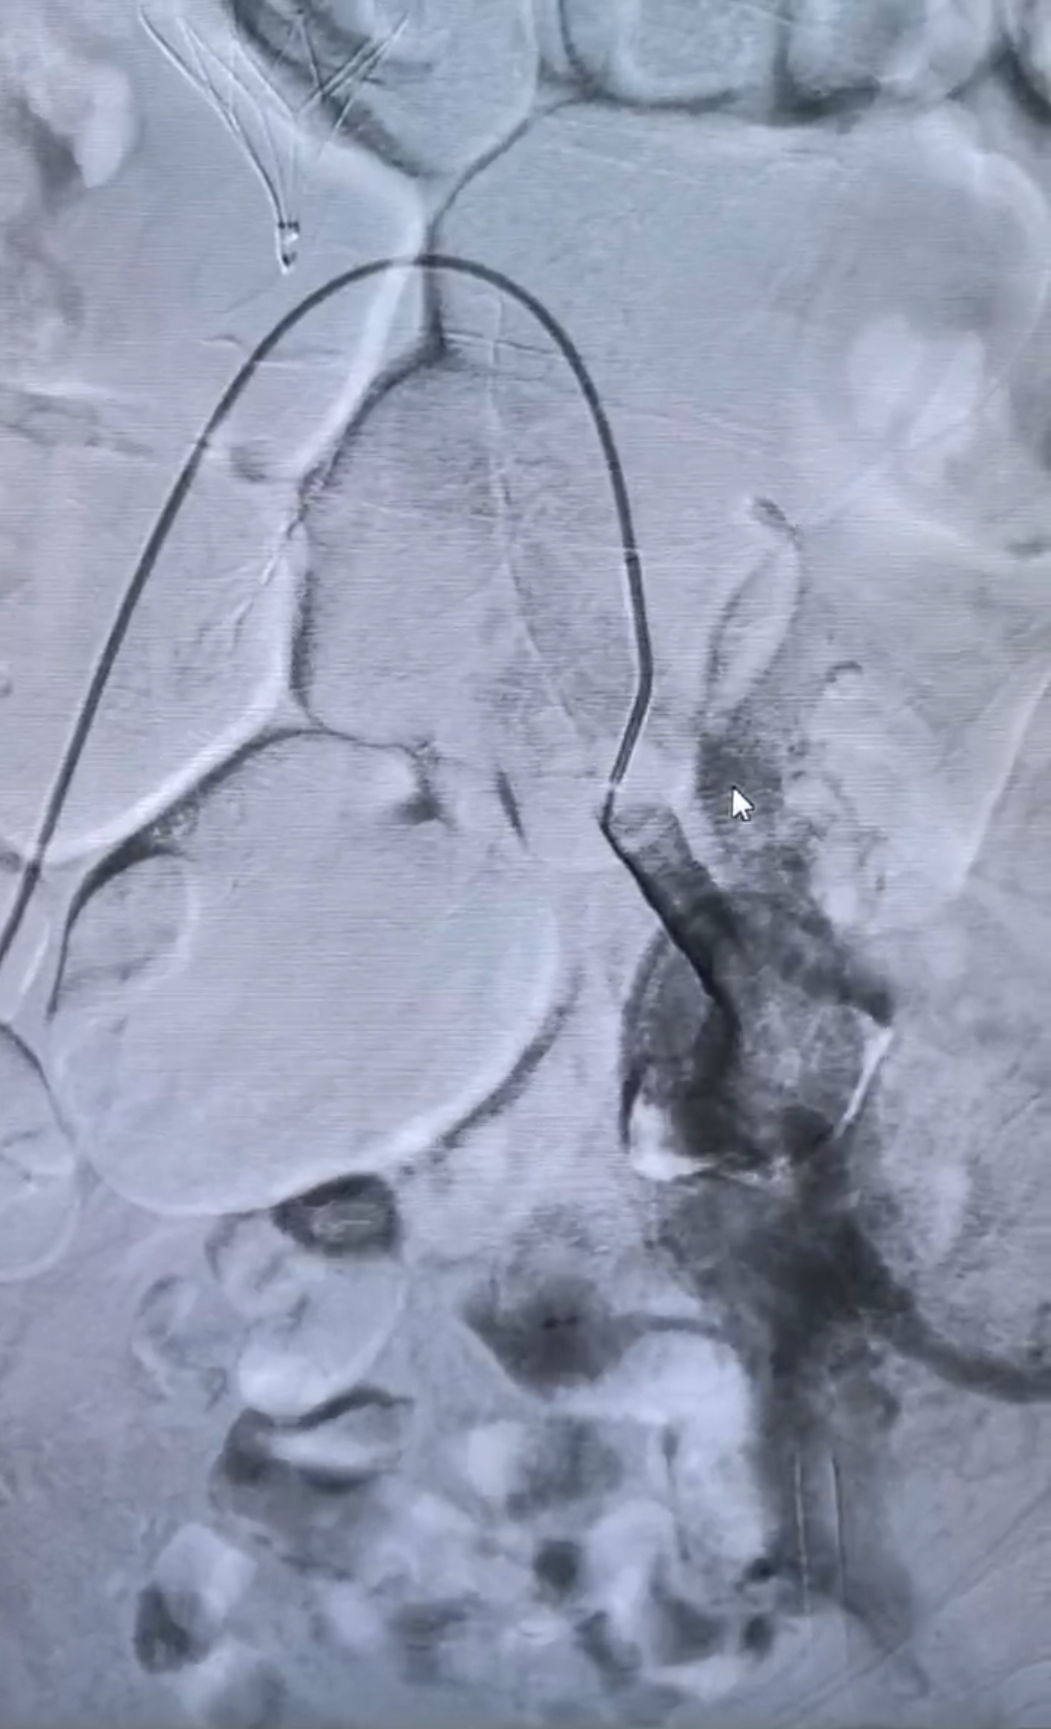

我院血管外科与介入科专家会诊后考虑患者出现股青肿表现,立即安排急诊手术。术中发现左髂静脉闭塞,股静脉逆向快速血流;左侧髂内动脉、左股动脉弥漫性动静脉瘘,前者为主,经左髂静脉回流。手术团队帮助患者开通闭塞的静脉并时刻保持血流通畅。术后第一天患者腿部就明显消肿,术后第二天腿部情况已与对侧基本一致。患者家属感叹,两年的老毛病,竟然一夜就消了。